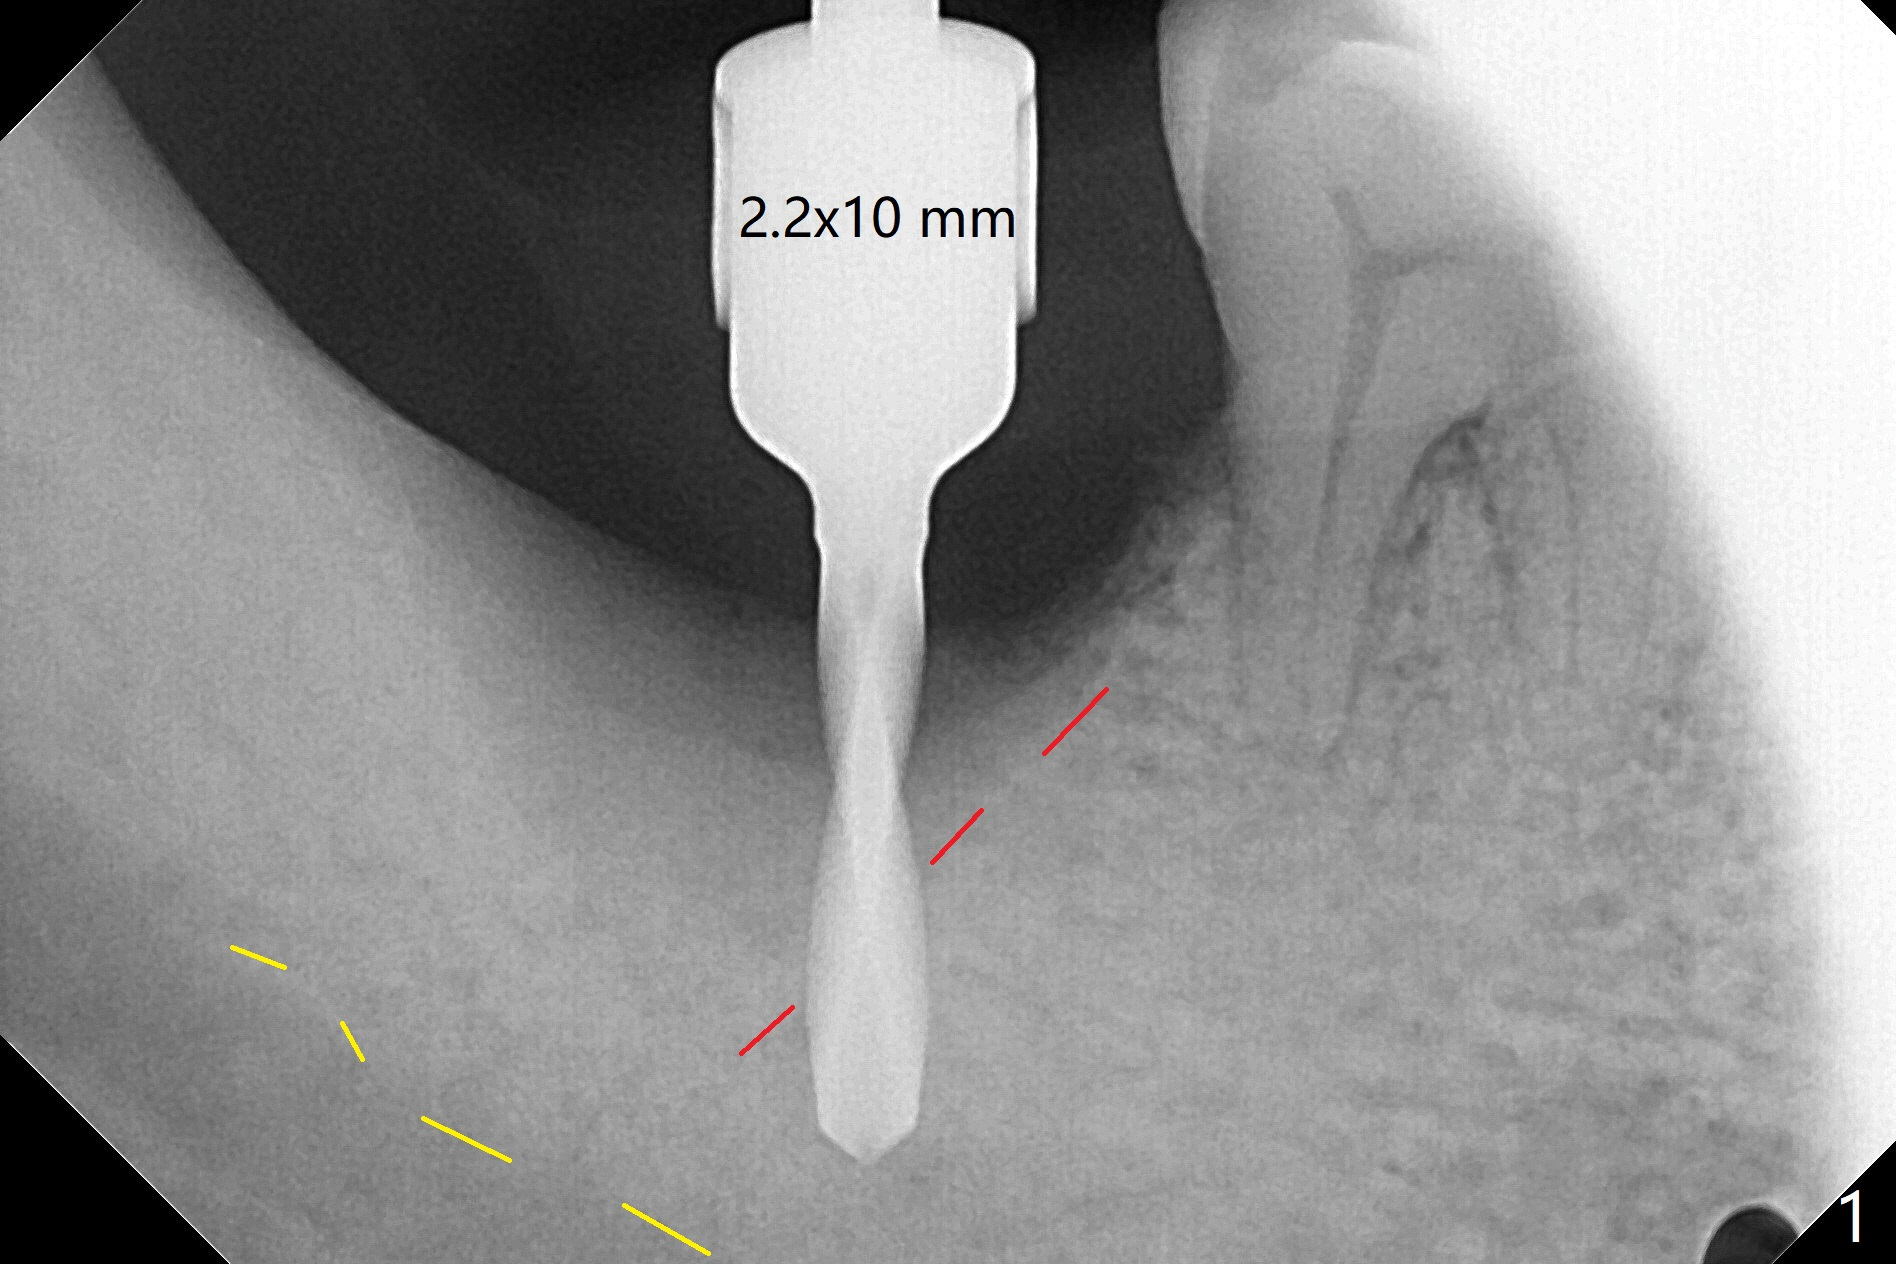

The morning case shows that to avoid Inferior Alveolar Neuropathy associated with 2nd molar implant placement, three measures should be adopted, no block anesthesia, no pressure on the distal end of the distal end guide and no over deep placement. In fact pain control is difficult with severe chronic periodontitis at #31. After repeated infiltration injection, the most effective step of anesthesia is slow speed of osteotomy with gentle pressure. The 1st intraop PA is taken when the depth is reached with a 2.2 mm pilot drill (Fig.1 (yellow dashed line: superior border of the Inferior Alveolar Canal)). The 2nd purpose of the PA is to make sure that the osteotomy is establish in the mesial slope of the socket (red dashed line). As drills increase in diameter, the patient experiences pain. Since the bone density is high, it is hard to place 5x10 mm implant to the lowest space (Fig.2 *, ~ 60 Ncm). For compensation, bone graft (Fig.3 *) is packed securely around the implant before and after abutment insertion. After fabrication of an immediate provisional, periodontal dressing is applied around the provisional and socket to prevent graft leakage. Smoke cessation/reduction is encouraged. In fact the patient returns 11 months postop (the 1st time postop), partly due to coronavirus. The immediate provisional is lost, but the distal defect has apparently been repaired (Fig.4*). A 4 mm cuff abutment is changed to due to enough occlusal clearance. The abutment is completely seated. Oral hygiene is poor with 1/2 ppd of smoke. SRP was done in the lower right quadrant when the implant was placed. When the crown is delivered 1 year postop, the patient mentions #18 mobility. SRP is done in the lower left quadrant. The bone is stable 10 months post cementation (Fig.5).